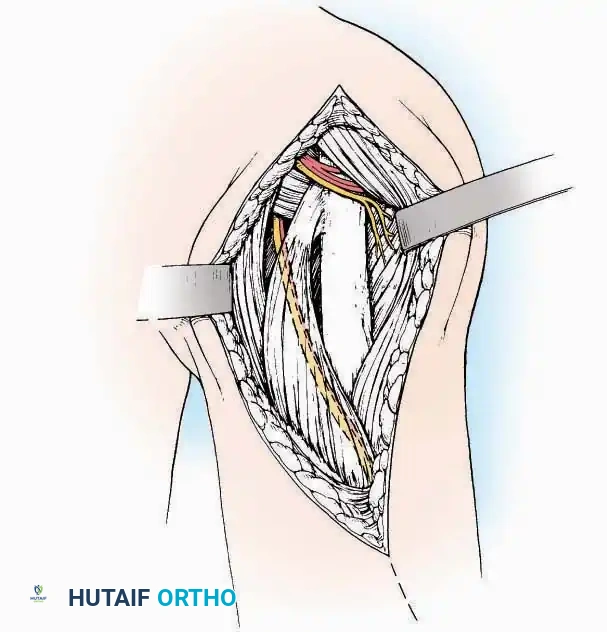

Anterolateral Approach

The anterolateral approach is widely considered the "universal incision" for the foot and ankle. It provides unparalleled access to the ankle joint, the talus, and the majority of the tarsal articulations, while safely avoiding the major anterior neurovascular bundle. The only tarsal joints inaccessible via this route are the naviculocuneiform joints (specifically the medial and intermediate).

Indications: Total talectomy, triple arthrodesis, ankle arthrodesis, and open reduction of complex talar neck fractures.

Surgical Technique:

* Incision: Begin over the anterolateral aspect of the leg, medial to the fibula and 5 cm proximal to the ankle joint line. Carry it distally over the joint, crossing the anterolateral aspect of the talar body and the calcaneocuboid joint, terminating at the base of the fourth metatarsal.

* Superficial Dissection: Incise the superficial fascia and the superior and inferior extensor retinacula down to the periosteum of the tibia and the ankle joint capsule.

* Vascular Ligation: This trajectory usually requires the identification and ligation of the anterolateral malleolar and lateral tarsal arteries.

* Nerve Protection: Retract the skin edges carefully. Identify and protect the intermediate dorsal cutaneous branches of the superficial peroneal nerve (SPN), which frequently cross the distal aspect of this incision.

* Muscle Management: Identify the origin of the extensor digitorum brevis (EDB) muscle on the lateral calcaneus. Divide it in the direction of its fibers, or detach its origin entirely and reflect it distally to expose the subtalar and calcaneocuboid joints.

* Deep Exposure: Retract the extensor digitorum longus (EDL) tendons, the dorsalis pedis artery, and the deep peroneal nerve (DPN) medially. Incise the anterior ankle capsule to expose the tibiotalar joint.

* Tarsal Exposure: Expose the talonavicular joint by dissecting deep to the extensor tendons and incising its capsule transversely. Continue laterally through the capsule of the calcaneocuboid joint. By excising the fat pad within the sinus tarsi (lateral and inferior to the talar neck), the posterior facet of the subtalar joint is brought into direct view.